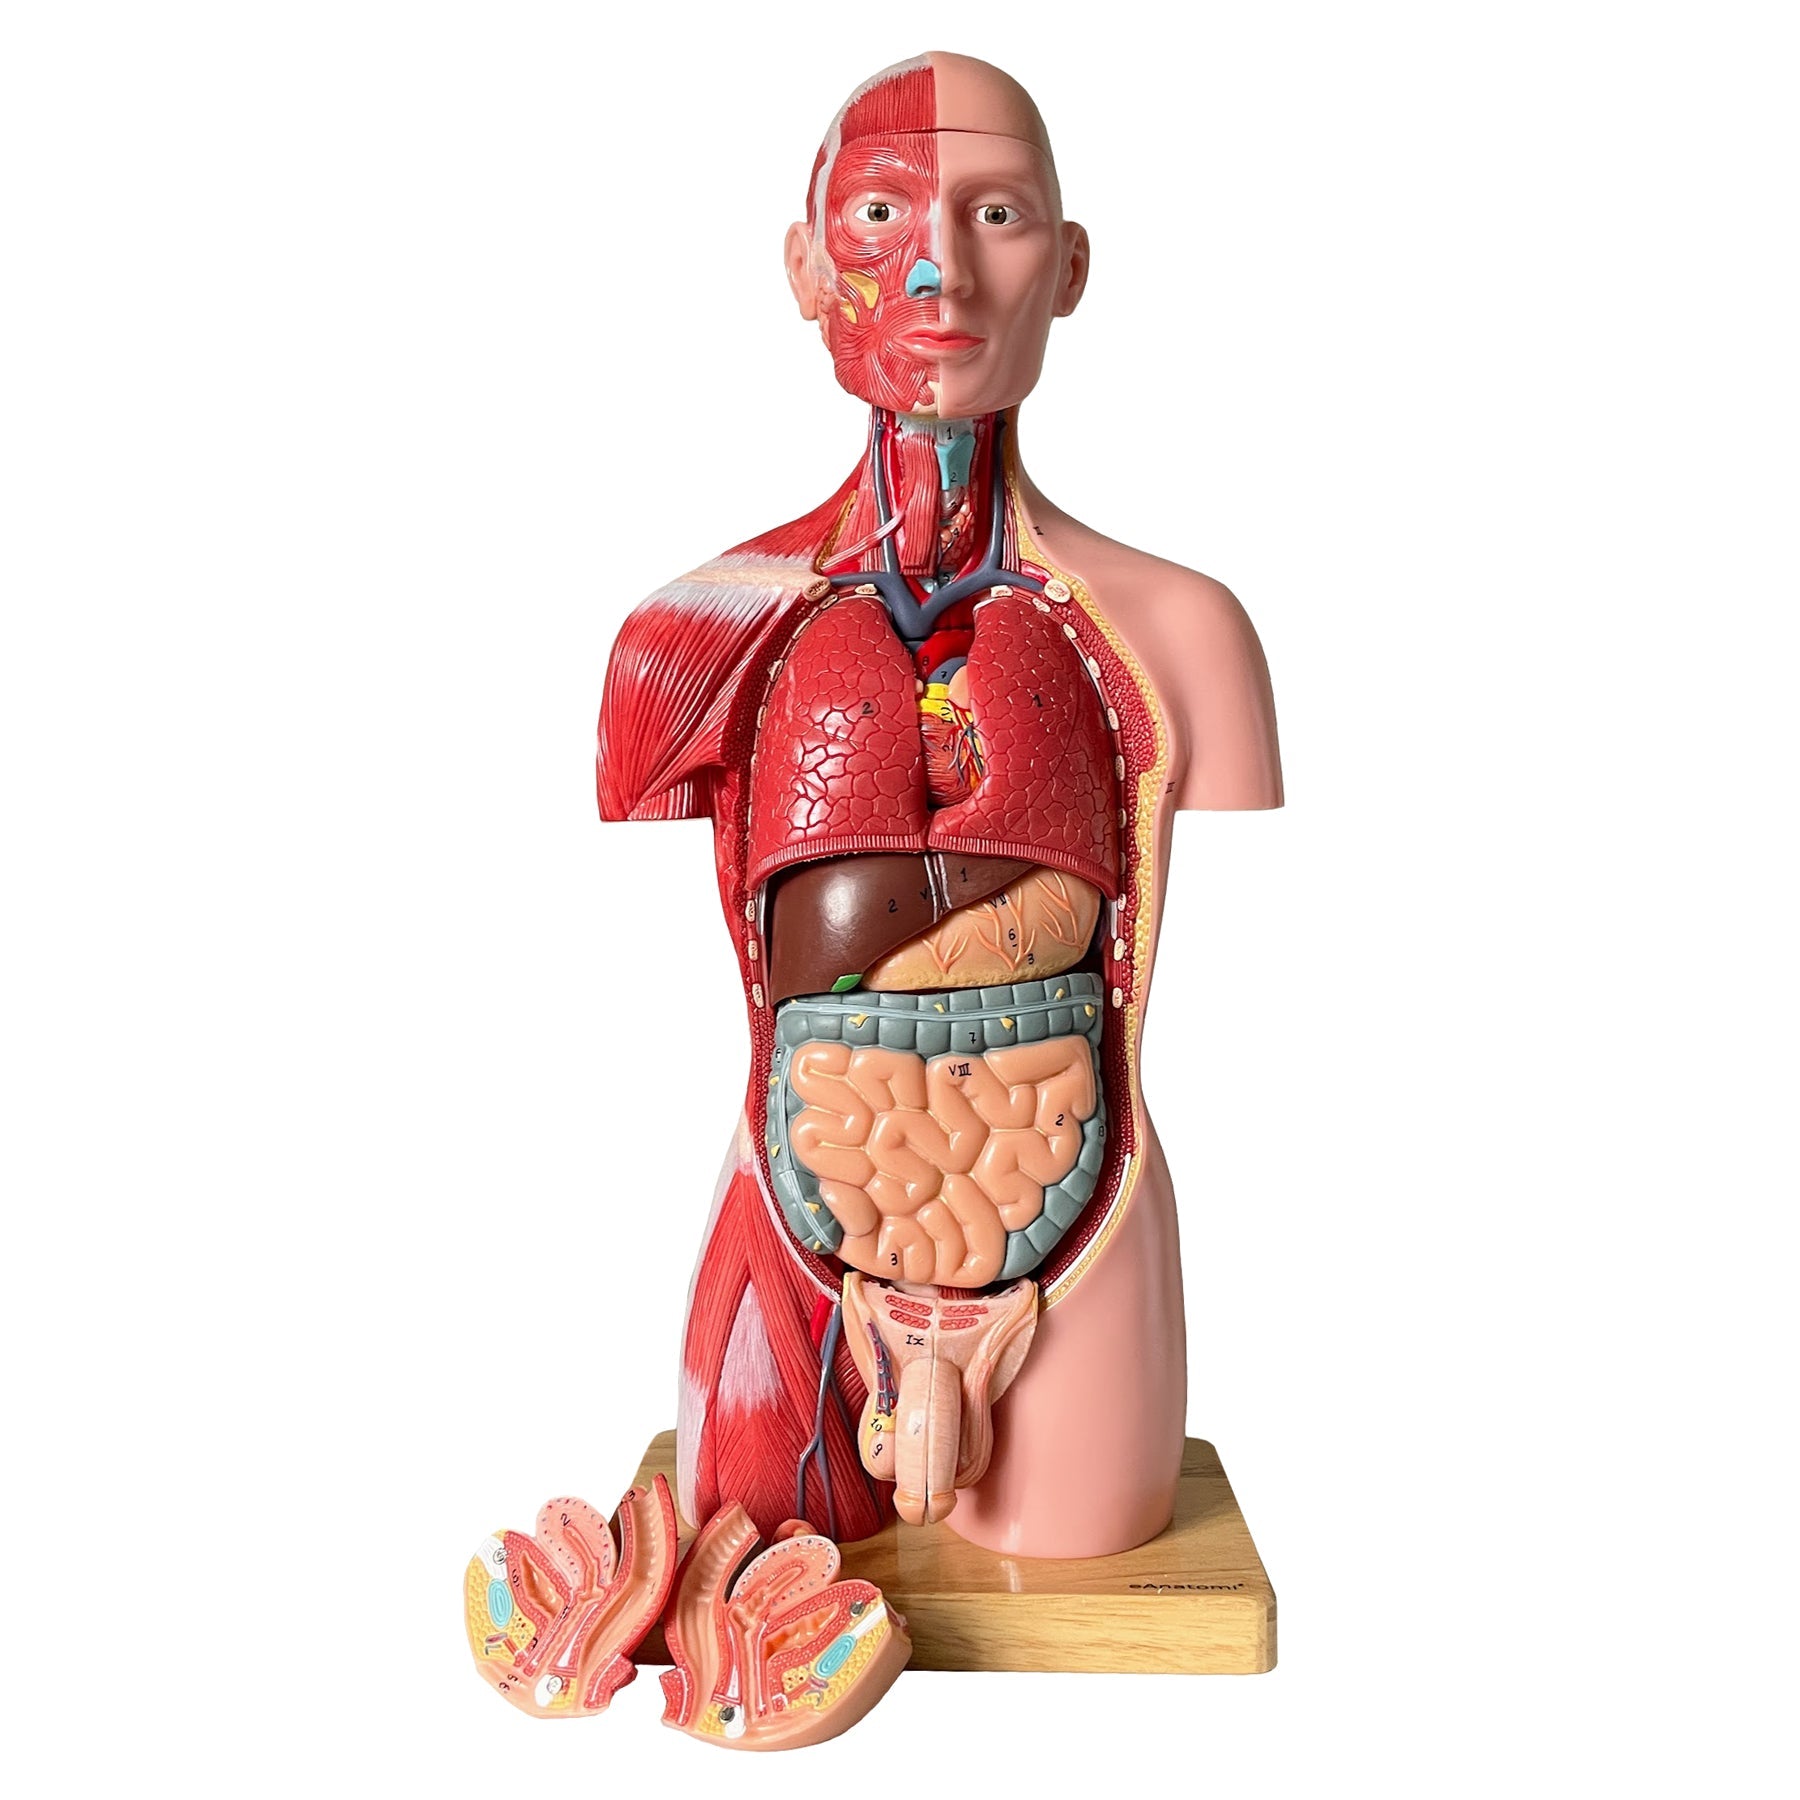

Med denne model får du det komplette overblik over hovedet og halsens anatomi. Modellen illustrere både den overfladiske og dybereliggende muskulatur, og viser desuden kar og nerver i relation til disse.

Modellen kan adskilles i 5 dele, idet kranietoppen kan aftages, og hjernen kan udtages og adskilles i 3 dele.

Modellen har målene 36 x 18 x 18 cm (højde x længde x bredde), vejer 2 kg og leveres på en hvid stander, som ligeledes er aftagelig.